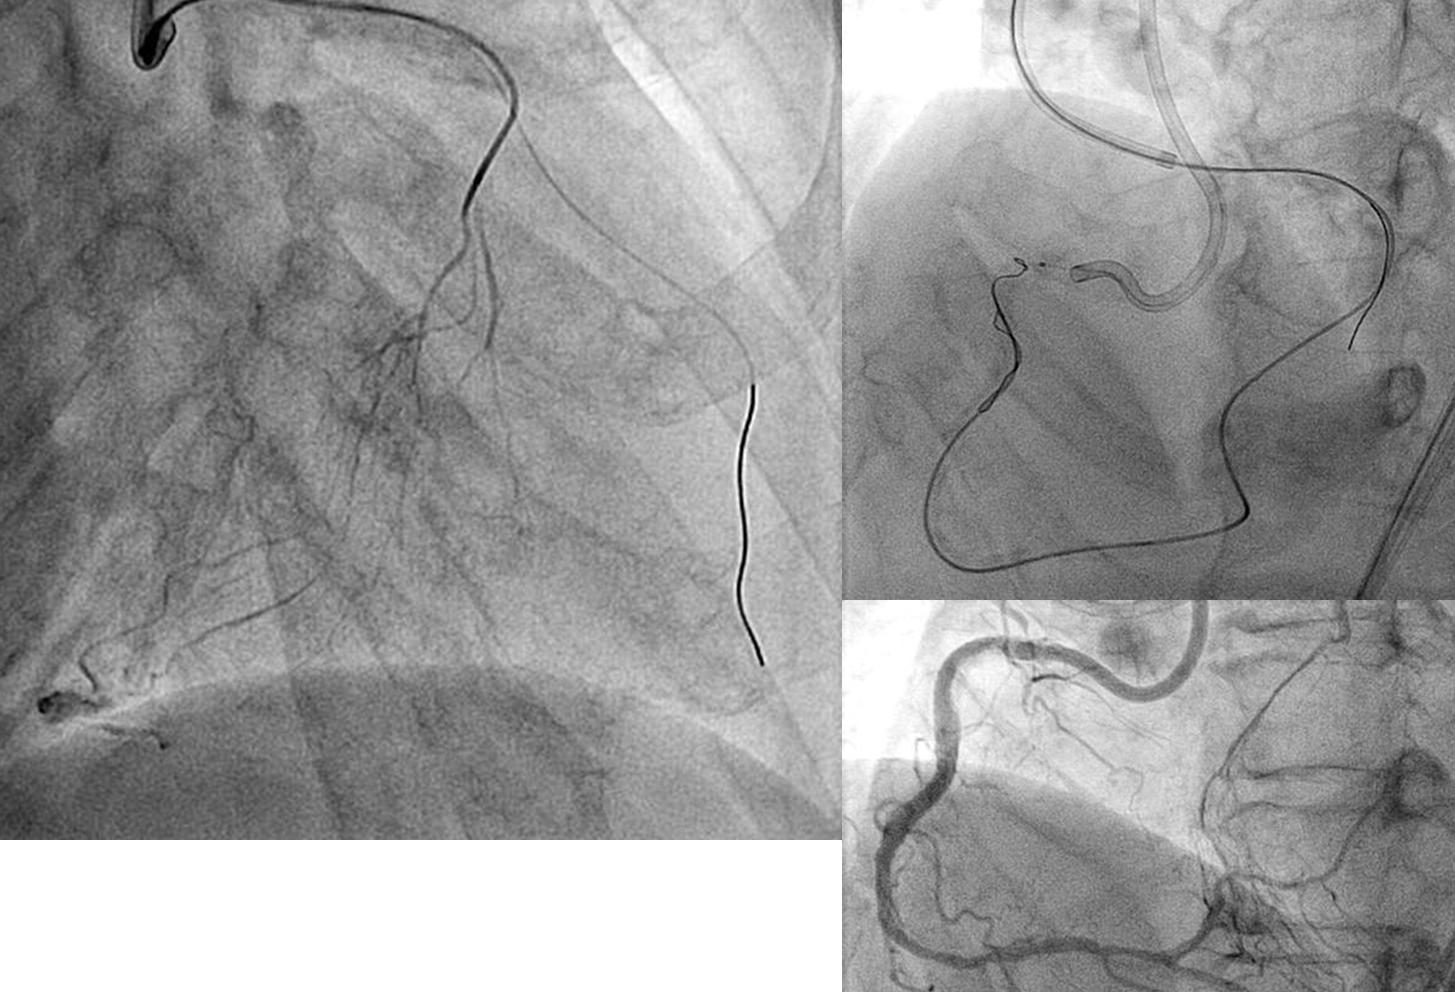

RCA CTO pilot GAIA2でPnctureできず、CP12でHDRもEPであり、その後にTDHDRを試みるも、石灰化でGWが一度はいるも、コルセアが通過できたが、HDRでType 2もその後にGWがEPにでてしまい。 TDADRで#3で穿刺した。plaqueが固く最...